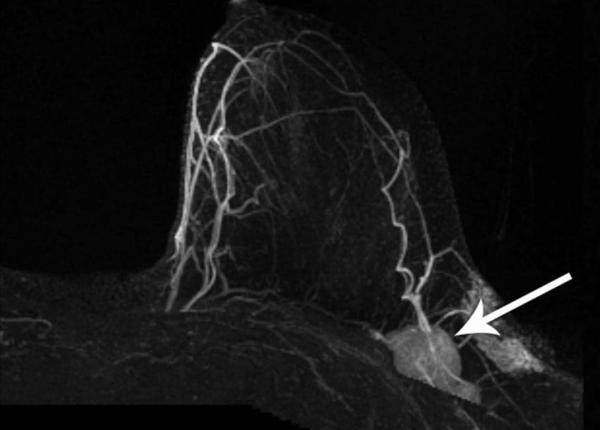

Vaccinul împotriva Covid ar putea afecta mamografia? Ce spun specialiștii